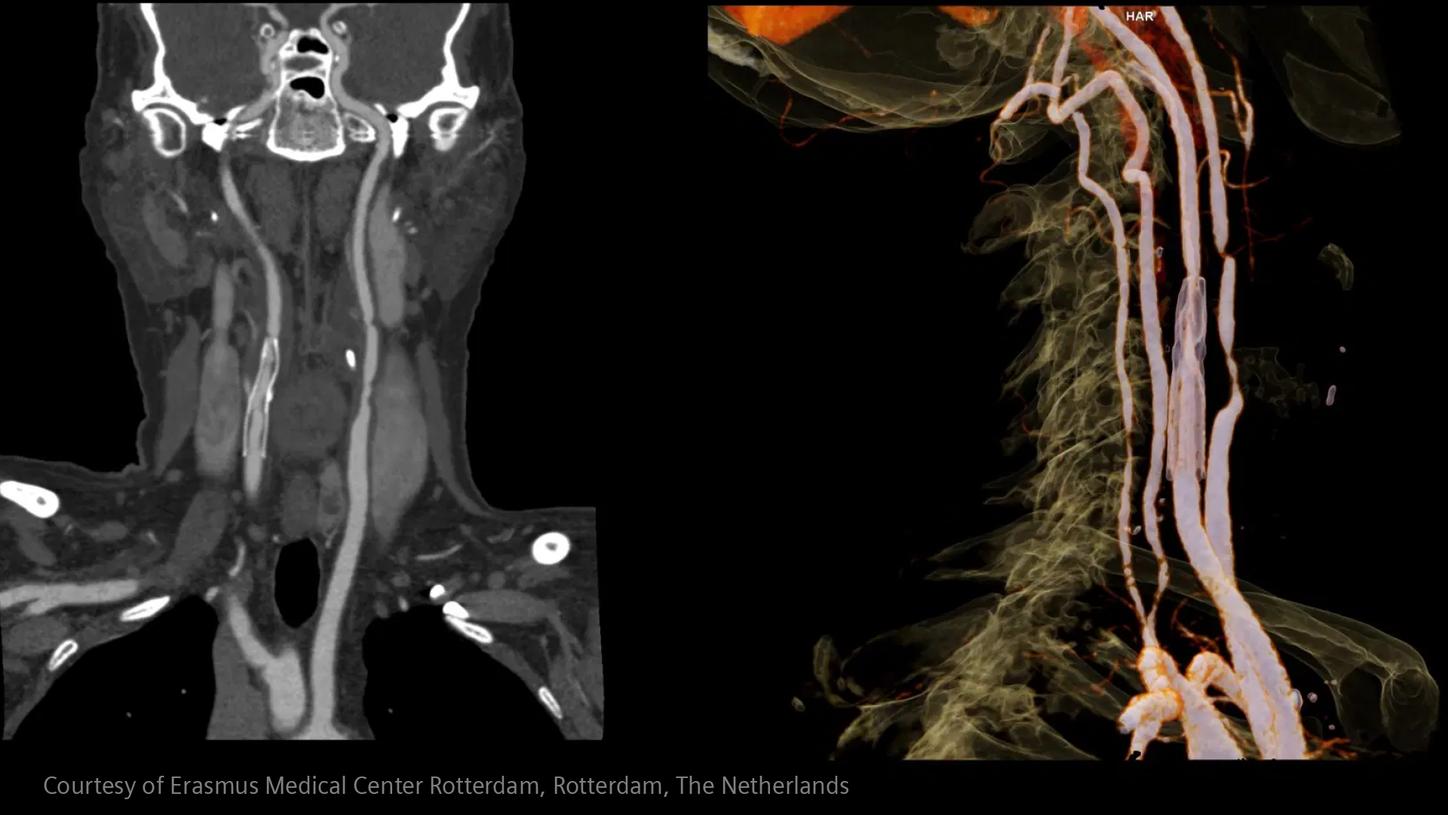

In stroke care, time is brain. Rapid and accurate imaging is crucial to assess the extent of brain injury and guide immediate treatment. Angiography, MRI, CT, ultrasound, and lab diagnostics are essential tools in identifying stroke type, location, and severity. Advances in imaging technology now allow for even faster acquisition, improved resolution, and enhanced visualization of brain tissue and blood vessels. Innovations such as perfusion imaging, real-time vascular mapping, and AI-assisted diagnostics are transforming stroke workflows and enabling precise, timely interventions.